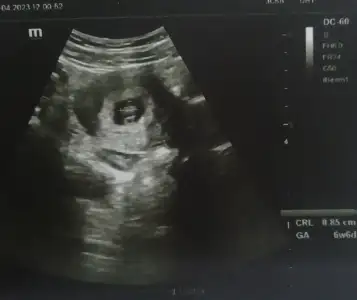

Bana da tahminde bulunur musunuz geçen attım herkes atınca arada kaynadı😂 ben tam anlamıyorum ortada mı sağda mı solda mı 😀

Eklentiler

• 89BE87E4-4101-4FF3-9AFE-C2BBE3B29736.webp

89BE87E4-4101-4FF3-9AFE-C2BBE3B29736.webp

27,6 KB · Görüntüleme: 82